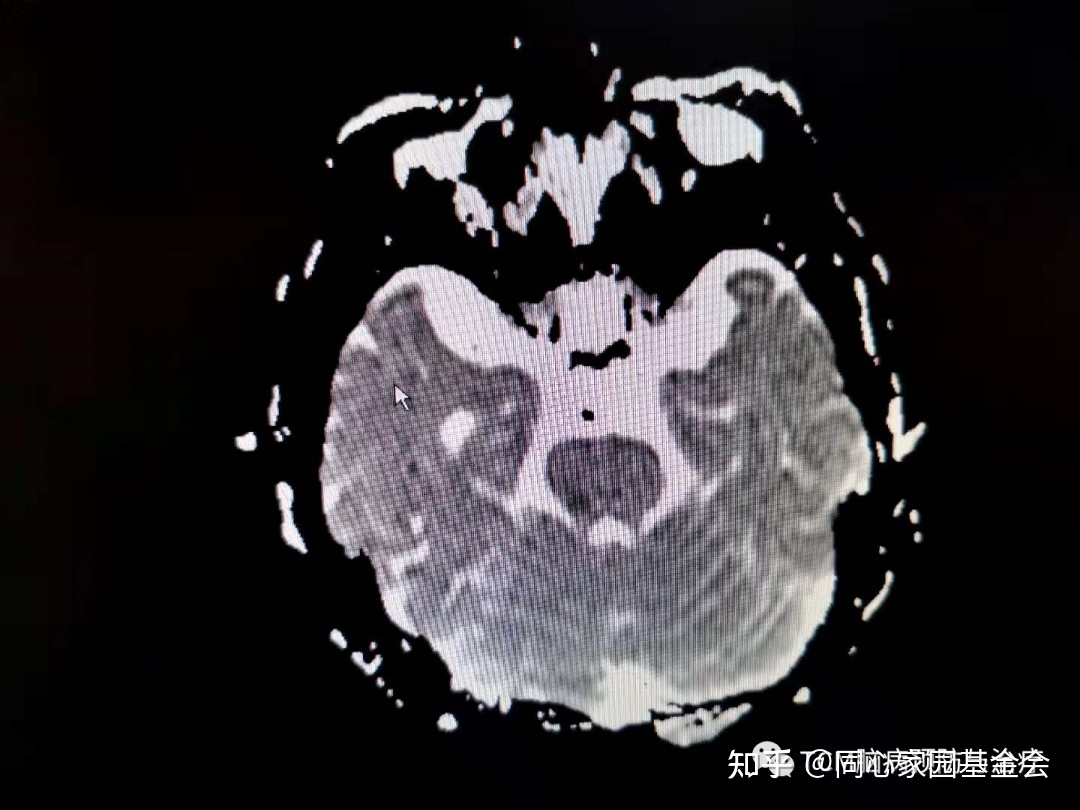

门诊查颅脑MRI如下:

诊断:急性脑梗死(桥脑),收入住院治疗,以急性脑梗死方案对症治疗。

PV合并脑血管病的临床特点:1.以血管病为首发症状的患者其本身症状可不明显,仅按脑梗死治疗欠佳并可在短期内多次发生脑卒中,其表现为多灶性改变,以多发性脑梗死最常见;2.影像学检查脑梗死以小灶型为主,表现为腔隙性脑梗死,常累及双侧,病灶主要见于脑叶、基底节、内囊;3.年龄多见于50岁左右,具有其原发病征象如颜面、口鼻、肢端红紫、疼痛,血常规与骨髓细胞学检查对本病有重要的诊断意义。